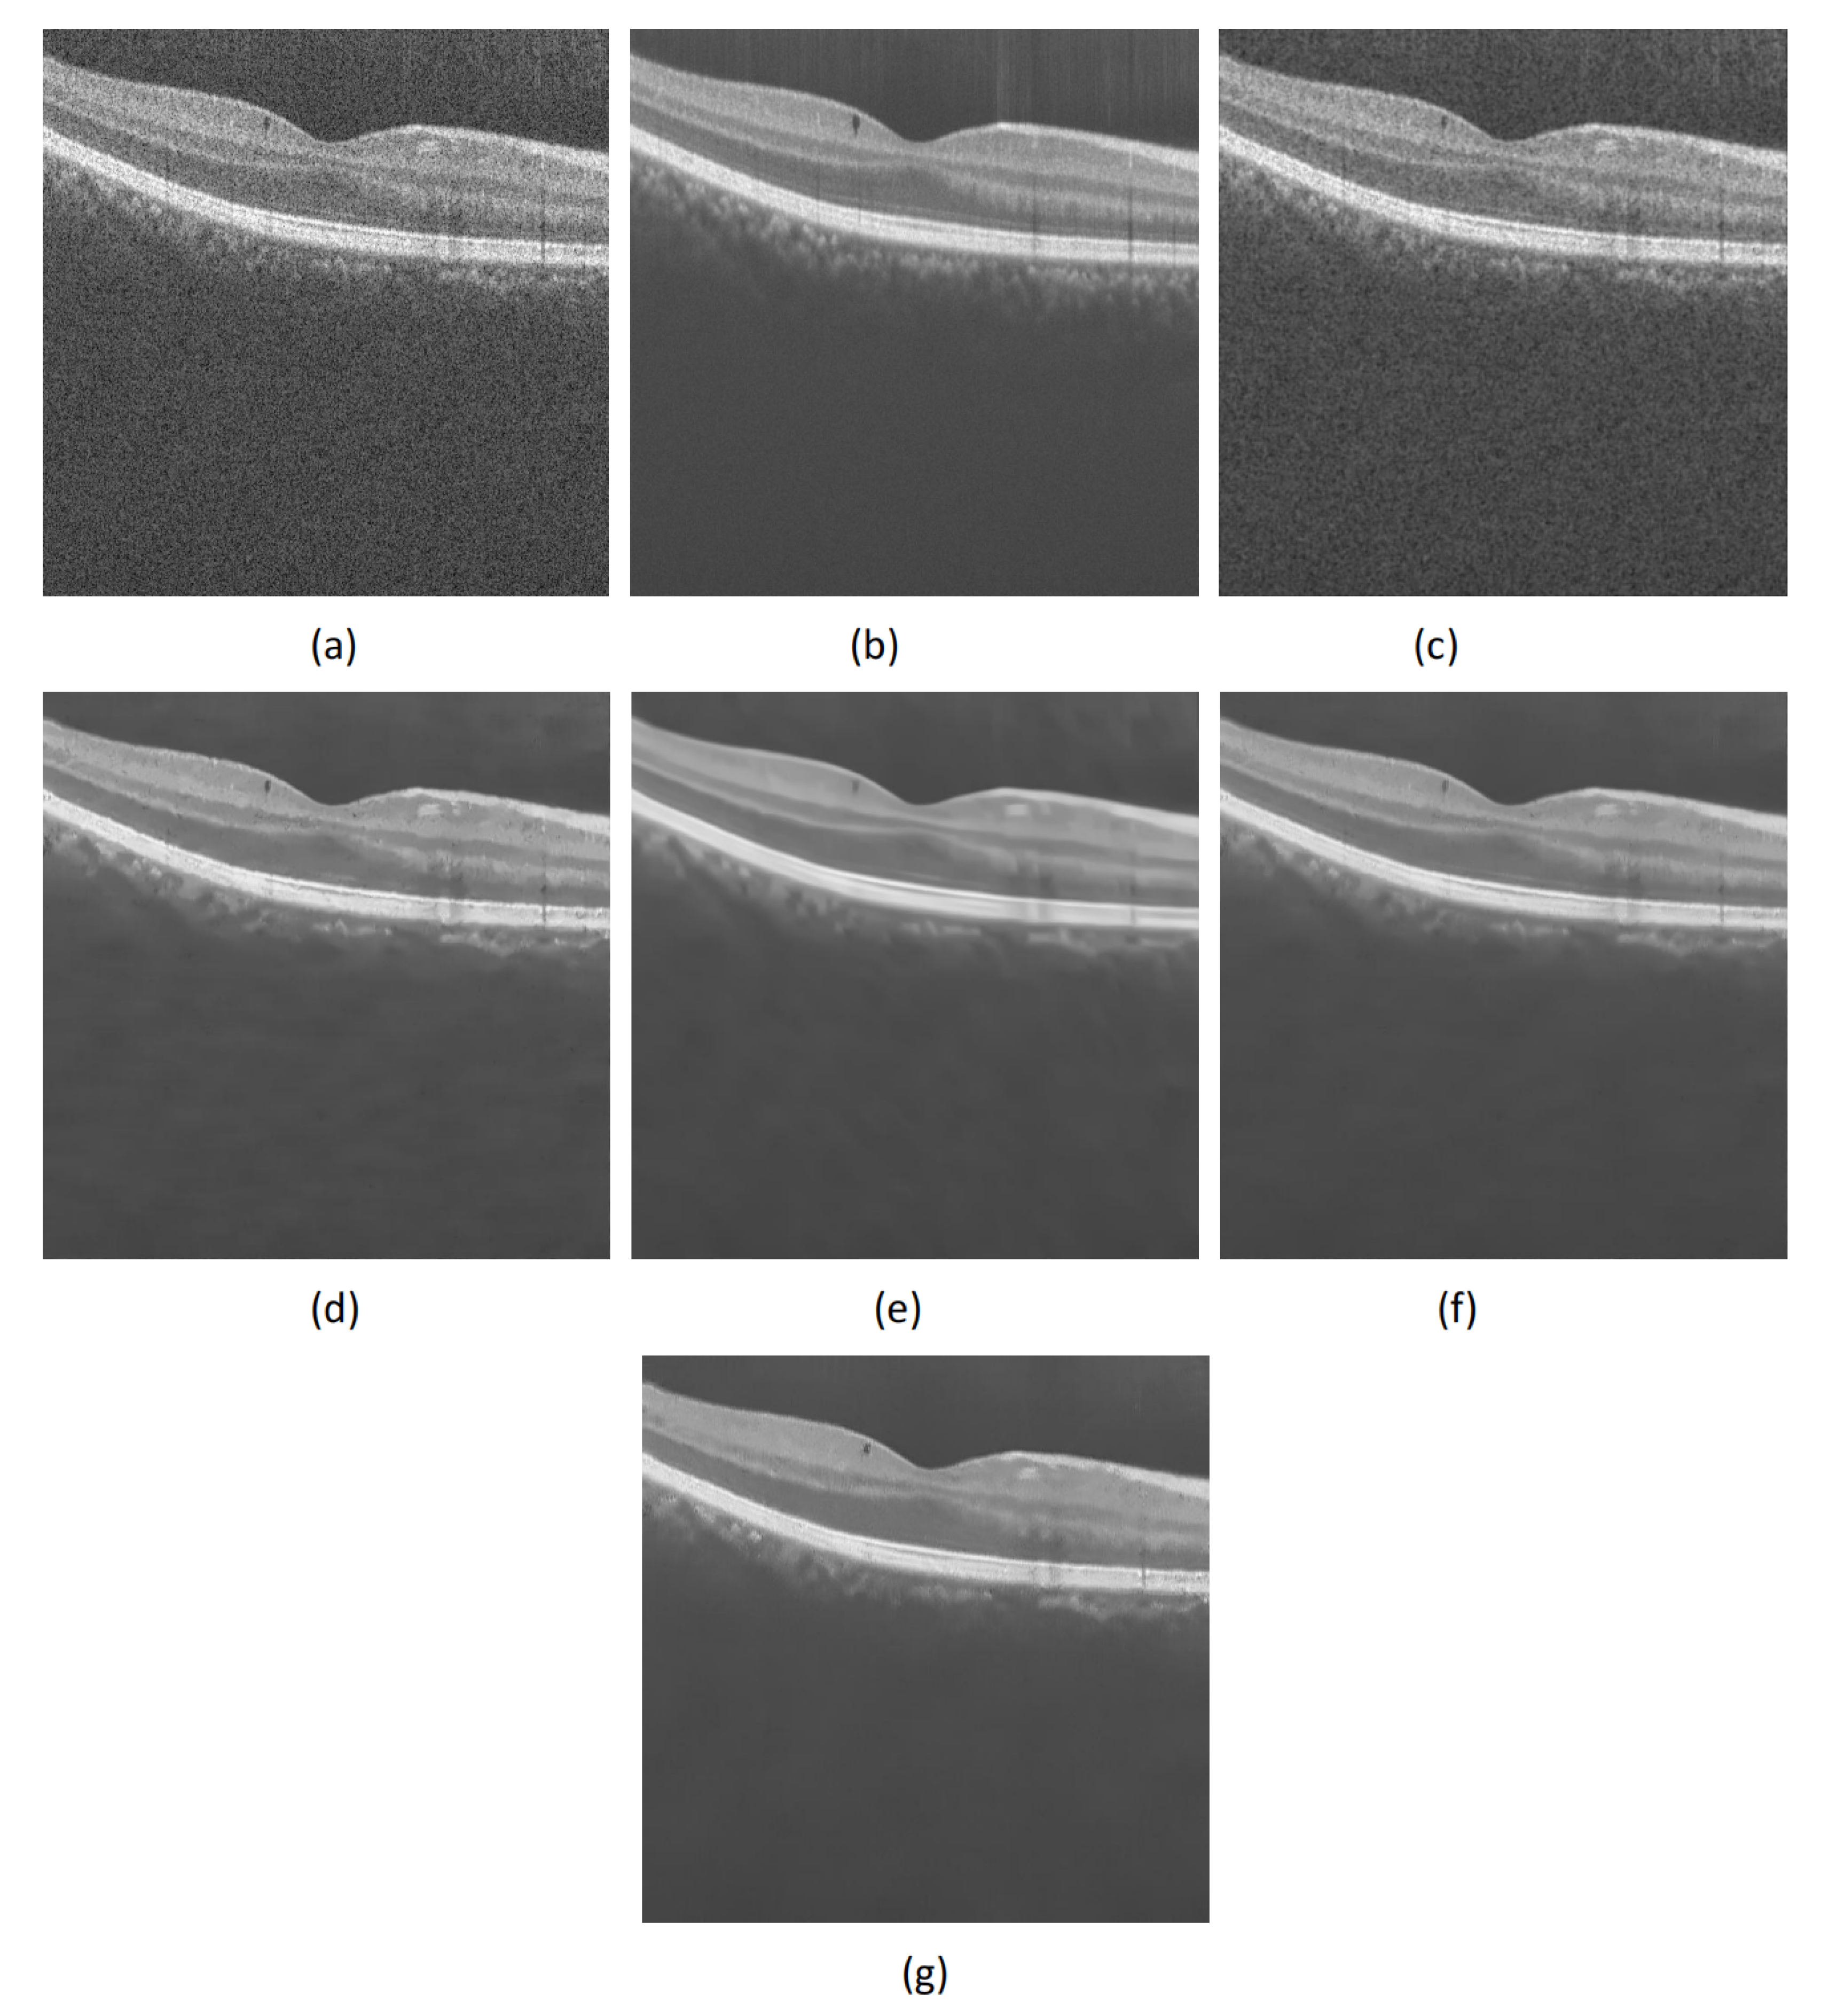

2.1. Visual Analysis of Real OCT Image Despeckling

2.4. Visual Analysis on OCT Data